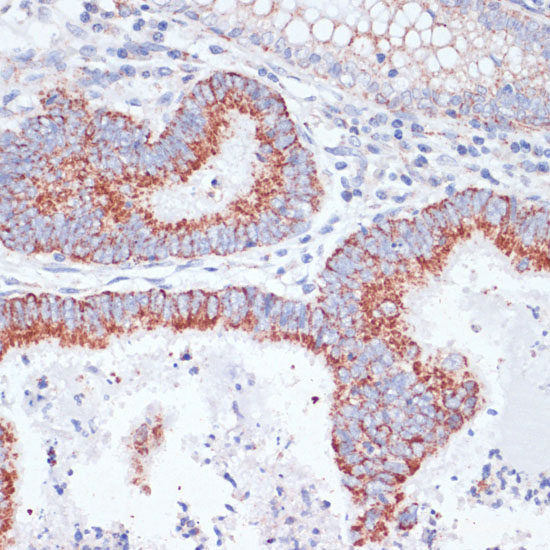

Product information "Anti-CD71"

This gene encodes a cell surface receptor necessary for cellular iron uptake by the process of receptor-mediated endocytosis. This receptor is required for erythropoiesis and neurologic development. Multiple alternatively spliced variants have been identified. Protein function: Cellular uptake of iron occurs via receptor-mediated endocytosis of ligand-occupied transferrin receptor into specialized endosomes. Endosomal acidification leads to iron release. The apotransferrin-receptor complex is then recycled to the cell surface with a return to neutral pH and the concomitant loss of affinity of apotransferrin for its receptor. Transferrin receptor is necessary for development of erythrocytes and the nervous system. A second ligand, the heditary hemochromatosis protein HFE, competes for binding with transferrin for an overlapping C-terminal binding site. Positively regulates T and B cell proliferation through iron uptake (PubMed:26642240). [The UniProt Consortium]

| Keywords: | Anti-TFRC, CD71 Polyclonal Antibody |

| Supplier: | Elabscience |

| Supplier-Nr: | E-AB-61161 |

| Application: | WB |

| Antibody Type: | Polyclonal |

| Conjugate: | No |

| Host: | Rabbit |

| Species reactivity: | human, mouse, rat |

| Immunogen: | Recombinant protein of human TFRC |